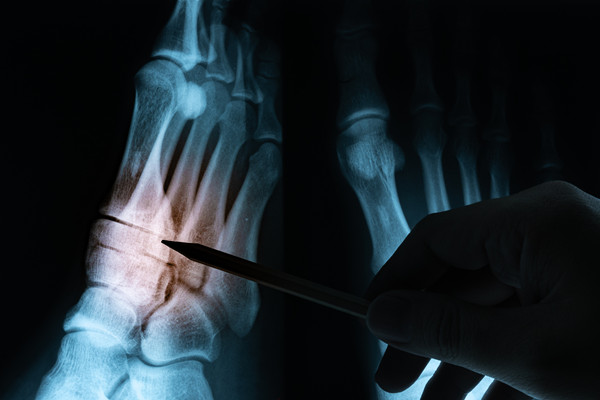

对于骨结核疾病尤其是对于无结核病史的患者出现骨头疼痛等症状时,早期应该做相应部位的影像检查如X线检查、MRI、CT检查。另外还需要做结核相关的实验室检查,例如ESR、CRP、PCT、血常规等检查,但出现异常这些检查指标会有增高。当然,对于部分骨肿瘤患者以及一般感染患者,也会存在这些检查的异常。所以为明确诊断,需要广大的患者朋友进一步行T-spot、结核分枝杆菌特异性抗体检测。